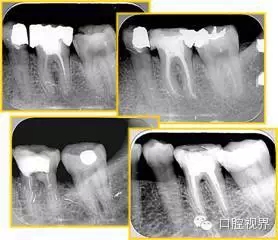

6. 術(shù)后 X 線片

術(shù)后 X 線片用來評定根管充填 長度、致密度(管壁清晰、側(cè)枝)等指標(biāo)。

左圖為根管充填術(shù)后 X 線片。圖中可見,根管充填較好。右下圖有白色小點(diǎn),為側(cè)方加壓導(dǎo)致糊劑擠出所致,表明根管充填比較致密。

致密、恰到好處的充填可去除干凈根管里感染灶,機(jī)體逐漸恢復(fù)。

多根牙時候需進(jìn)行偏移投照,正位投照無法說明具體哪根牙根管充填效果。